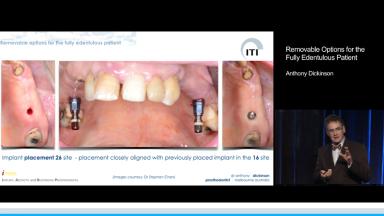

Removable Options for the Fully Edentulous Patient

This lecture presents the realistic expectations for removable prosthetic therapy from the perspective of the geriatric patient: primarily, an esthetic and functional outcome with long-term stability and low risk of complications; and secondarily, the least number of surgical interventions, the least possible pain and morbidity, and a cost-effective treatment.To fulfill these expectations, a common-sense management protocol for geriatric patients is presented and illustrated using two well-documented clinical cases. This lecture emphasizes an appropriate therapeutic sequence to achieve the planned outcome, the goal of which is to transition the patient in manageable stages, thereby reducing the adaptive requirements during therapy.